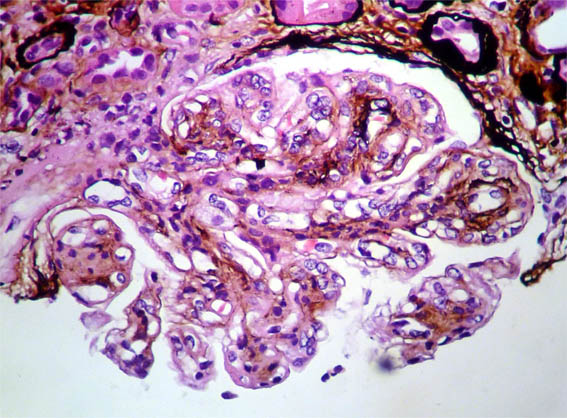

Figure 9. Direct immunfluorescence for IgG, X400.